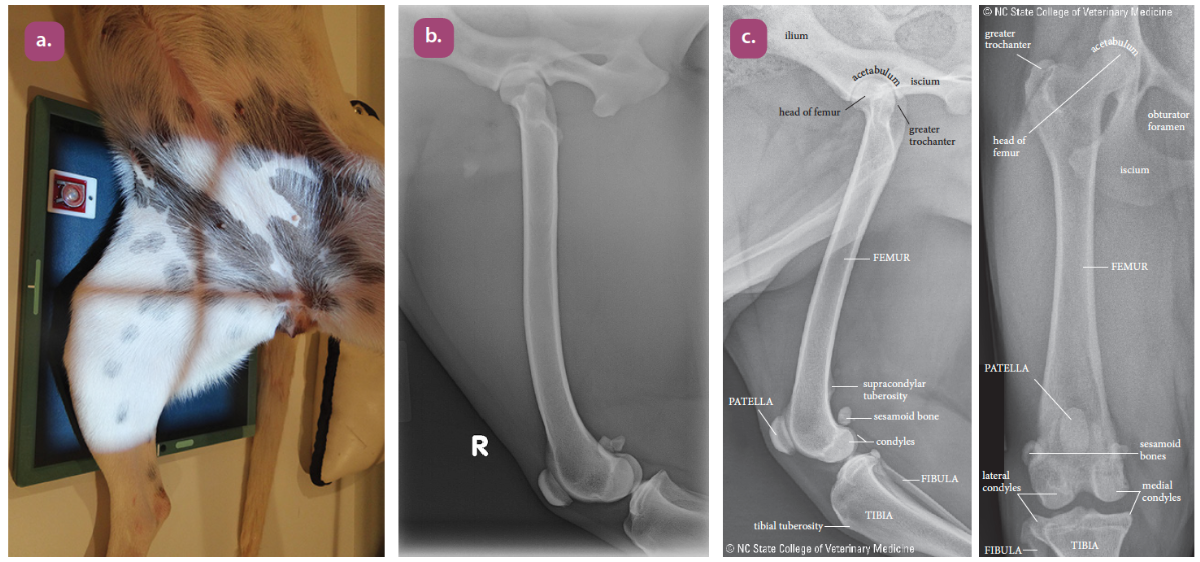

mediolateral projection of the femur

Craniocaudal projection of the femur